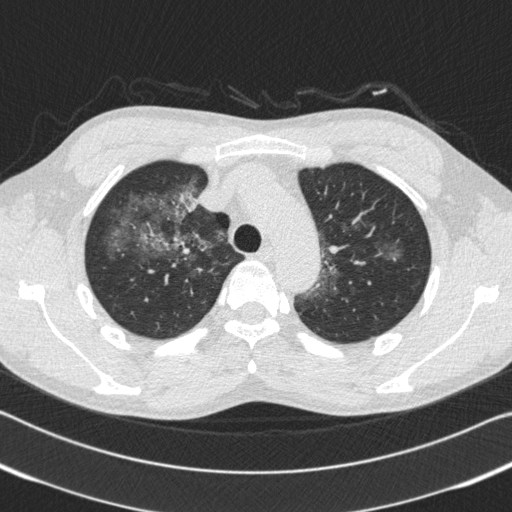

2013-05-06 chest CT(1)